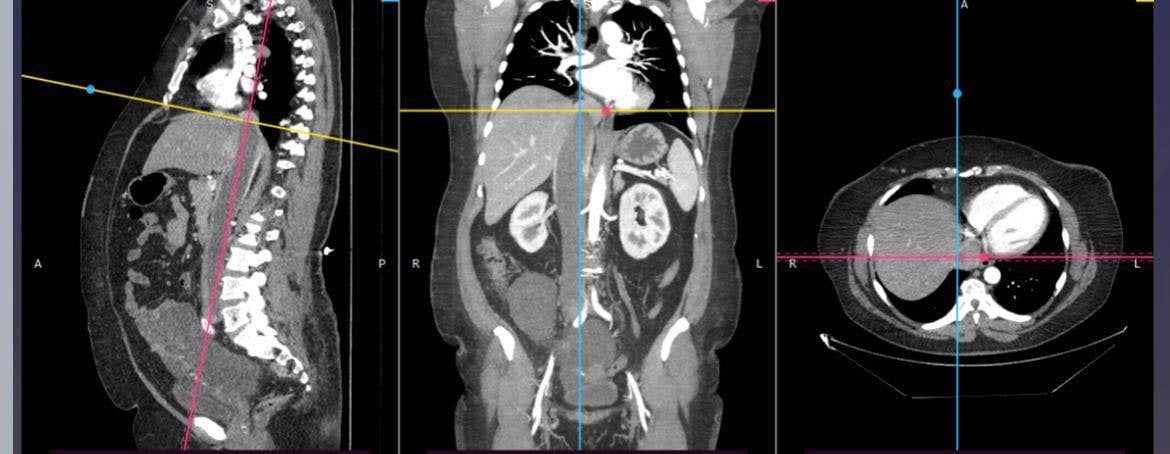

Зображення пухлини, яка дісталася до серця / © Університетська лікарня ЛНМУ імені Данила Галицького